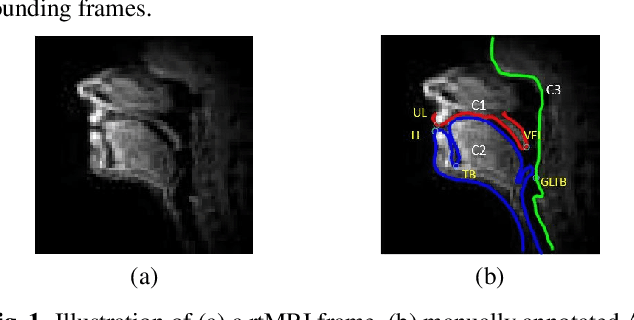

The best performance in Air-tissue boundary (ATB) segmentation of real-time Magnetic Resonance Imaging (rtMRI) videos in speech production is known to be achieved by a 3-dimensional convolutional neural network (3D-CNN) model. However, the evaluation of this model, as well as other ATB segmentation techniques reported in the literature, is done using Dynamic Time Warping (DTW) distance between the entire original and predicted contours. Such an evaluation measure may not capture local errors in the predicted contour. Careful analysis of predicted contours reveals errors in regions like the velum part of contour1 (ATB comprising of upper lip, hard palate, and velum) and tongue base section of contour2 (ATB covering jawline, lower lip, tongue base, and epiglottis), which are not captured in a global evaluation metric like DTW distance. In this work, we automatically detect such errors and propose a correction scheme for the same. We also propose two new evaluation metrics for ATB segmentation separately in contour1 and contour2 to explicitly capture two types of errors in these contours. The proposed detection and correction strategies result in an improvement of these two evaluation metrics by 61.8% and 61.4% for contour1 and by 67.8% and 28.4% for contour2. Traditional DTW distance, on the other hand, improves by 44.6% for contour1 and 4.0% for contour2.